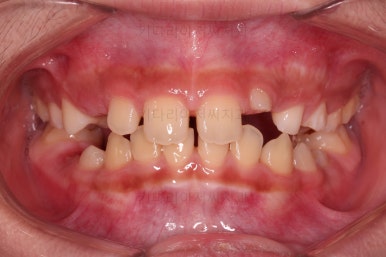

전후사진을 비교해 보겠습니다.

왼쪽이 부산어린이돌출입교정 치료 전, 오른쪽이 치료 후 입니다.

위치가 나빴던 앞니가 제위치로 갔고, 위아래 앞니도 서로 가까워졌어요.

앵글씨 2급 부정교합이 개선된거죠.

아래턱-위턱이 차이날 때 필연적으로 생기는 과개교합(앞니가 서로 깊게 맞물리는 교합)도 개선되었고요.

입이 튀어나와 보이던 모습도 완벽히 개선되었어요.

아래턱이 작아보이던 모습독 개선되었고 입도 편안하게 다물어져요.

턱의 위치가 잘못되어 결과적으로 보이던 "입이 튀어나온 모습, 윗니가 튀어나온 모습"이 턱뼈의 위치를 바로 잡아줌으로써 개선이 된거죠.